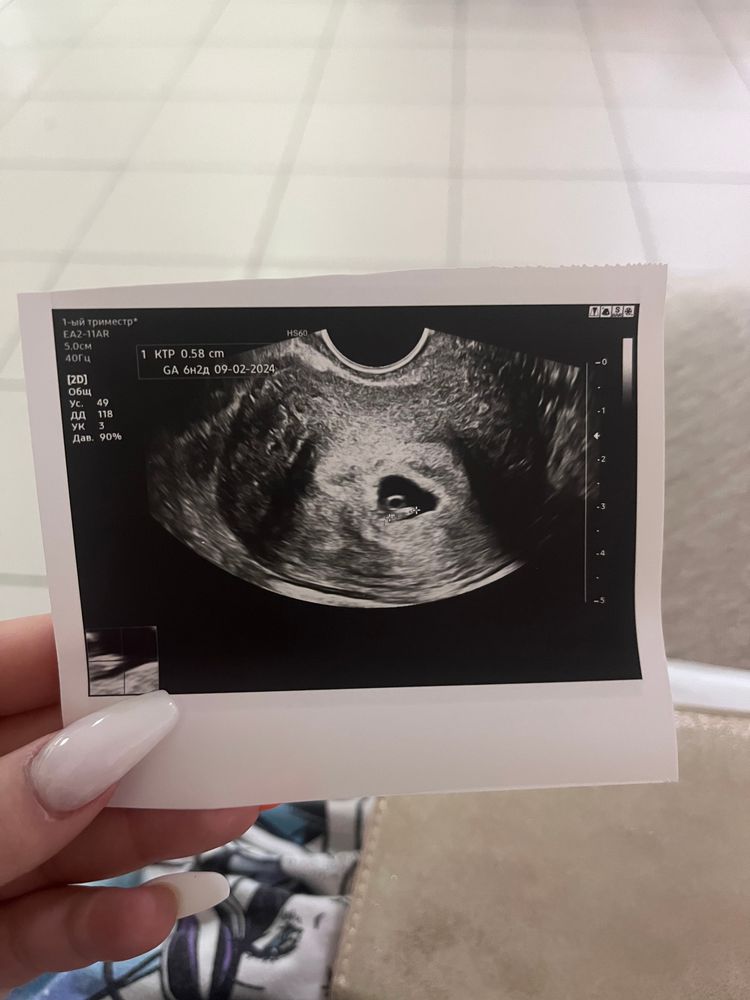

Узи 6 недель нет сердцебиения

Узи 6 недель нет сердцебиения 119 фотографий